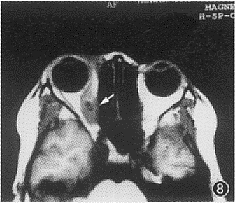

8 MRT 检查眶内 囊尾蚴病 (活动期),T1加权像右眼内直肌梭形增粗, 肌腹部可见一低信号囊泡, 囊泡内中低信号 (箭头) 为头节影